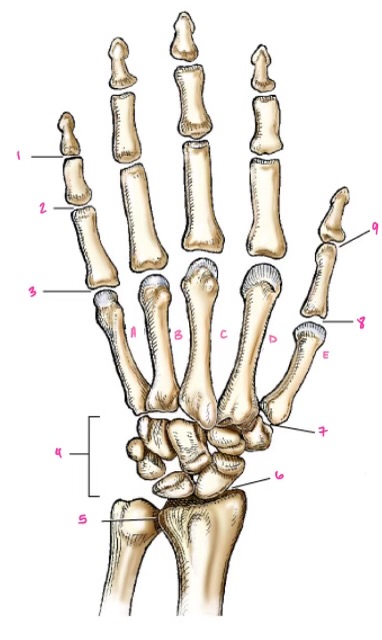

1

1

Hamate

2

2

Capitate

3

3

pisiform

4

9

Trapezoid

5

10

Trapezium

6

11

Scaphoid

7

14

Lunate

8

15

Triquetrum

9

16

Pisiform

10

17

Capitate

11

18

Hamate

1

Distal interphalangeal

13

2

Proximal Interphalangeal

14

3

Metacarpophalangeal

15

4

Intercapals

16

5

Distal radioulnar

17

6

Radiocarpal

18

7

Carpometacarpals

19

8

Metacarpophalangeal

20

9

Interphalangeal

7

Trapezoid

22

8

Trapzium

23

9

Capitate

24

10

Scaphoid

25

11

Lunate

26

13

Carpus

27

14

Triquetrul

28

15

Hamate

29

16

Metacarpus

30

17

Phalanxes